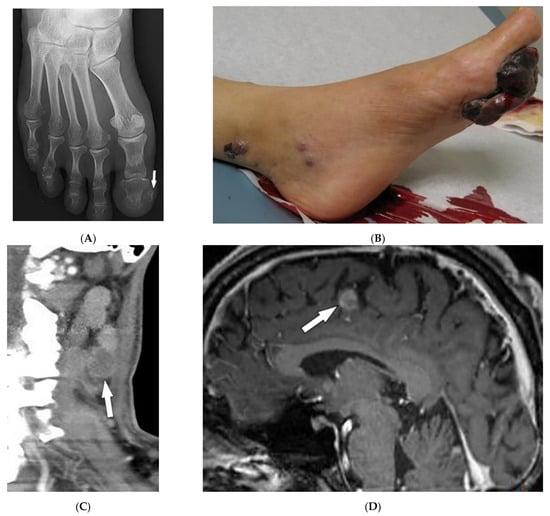

4.2. Kaposi Sarcoma

| Kaposi sarcoma | Erythematous or violaceous macules, plaques, nodules Pulmonary involvement Gastrointestinal involvement | Nodular enhancing masses Peribroncovascular nodules and halo sign |